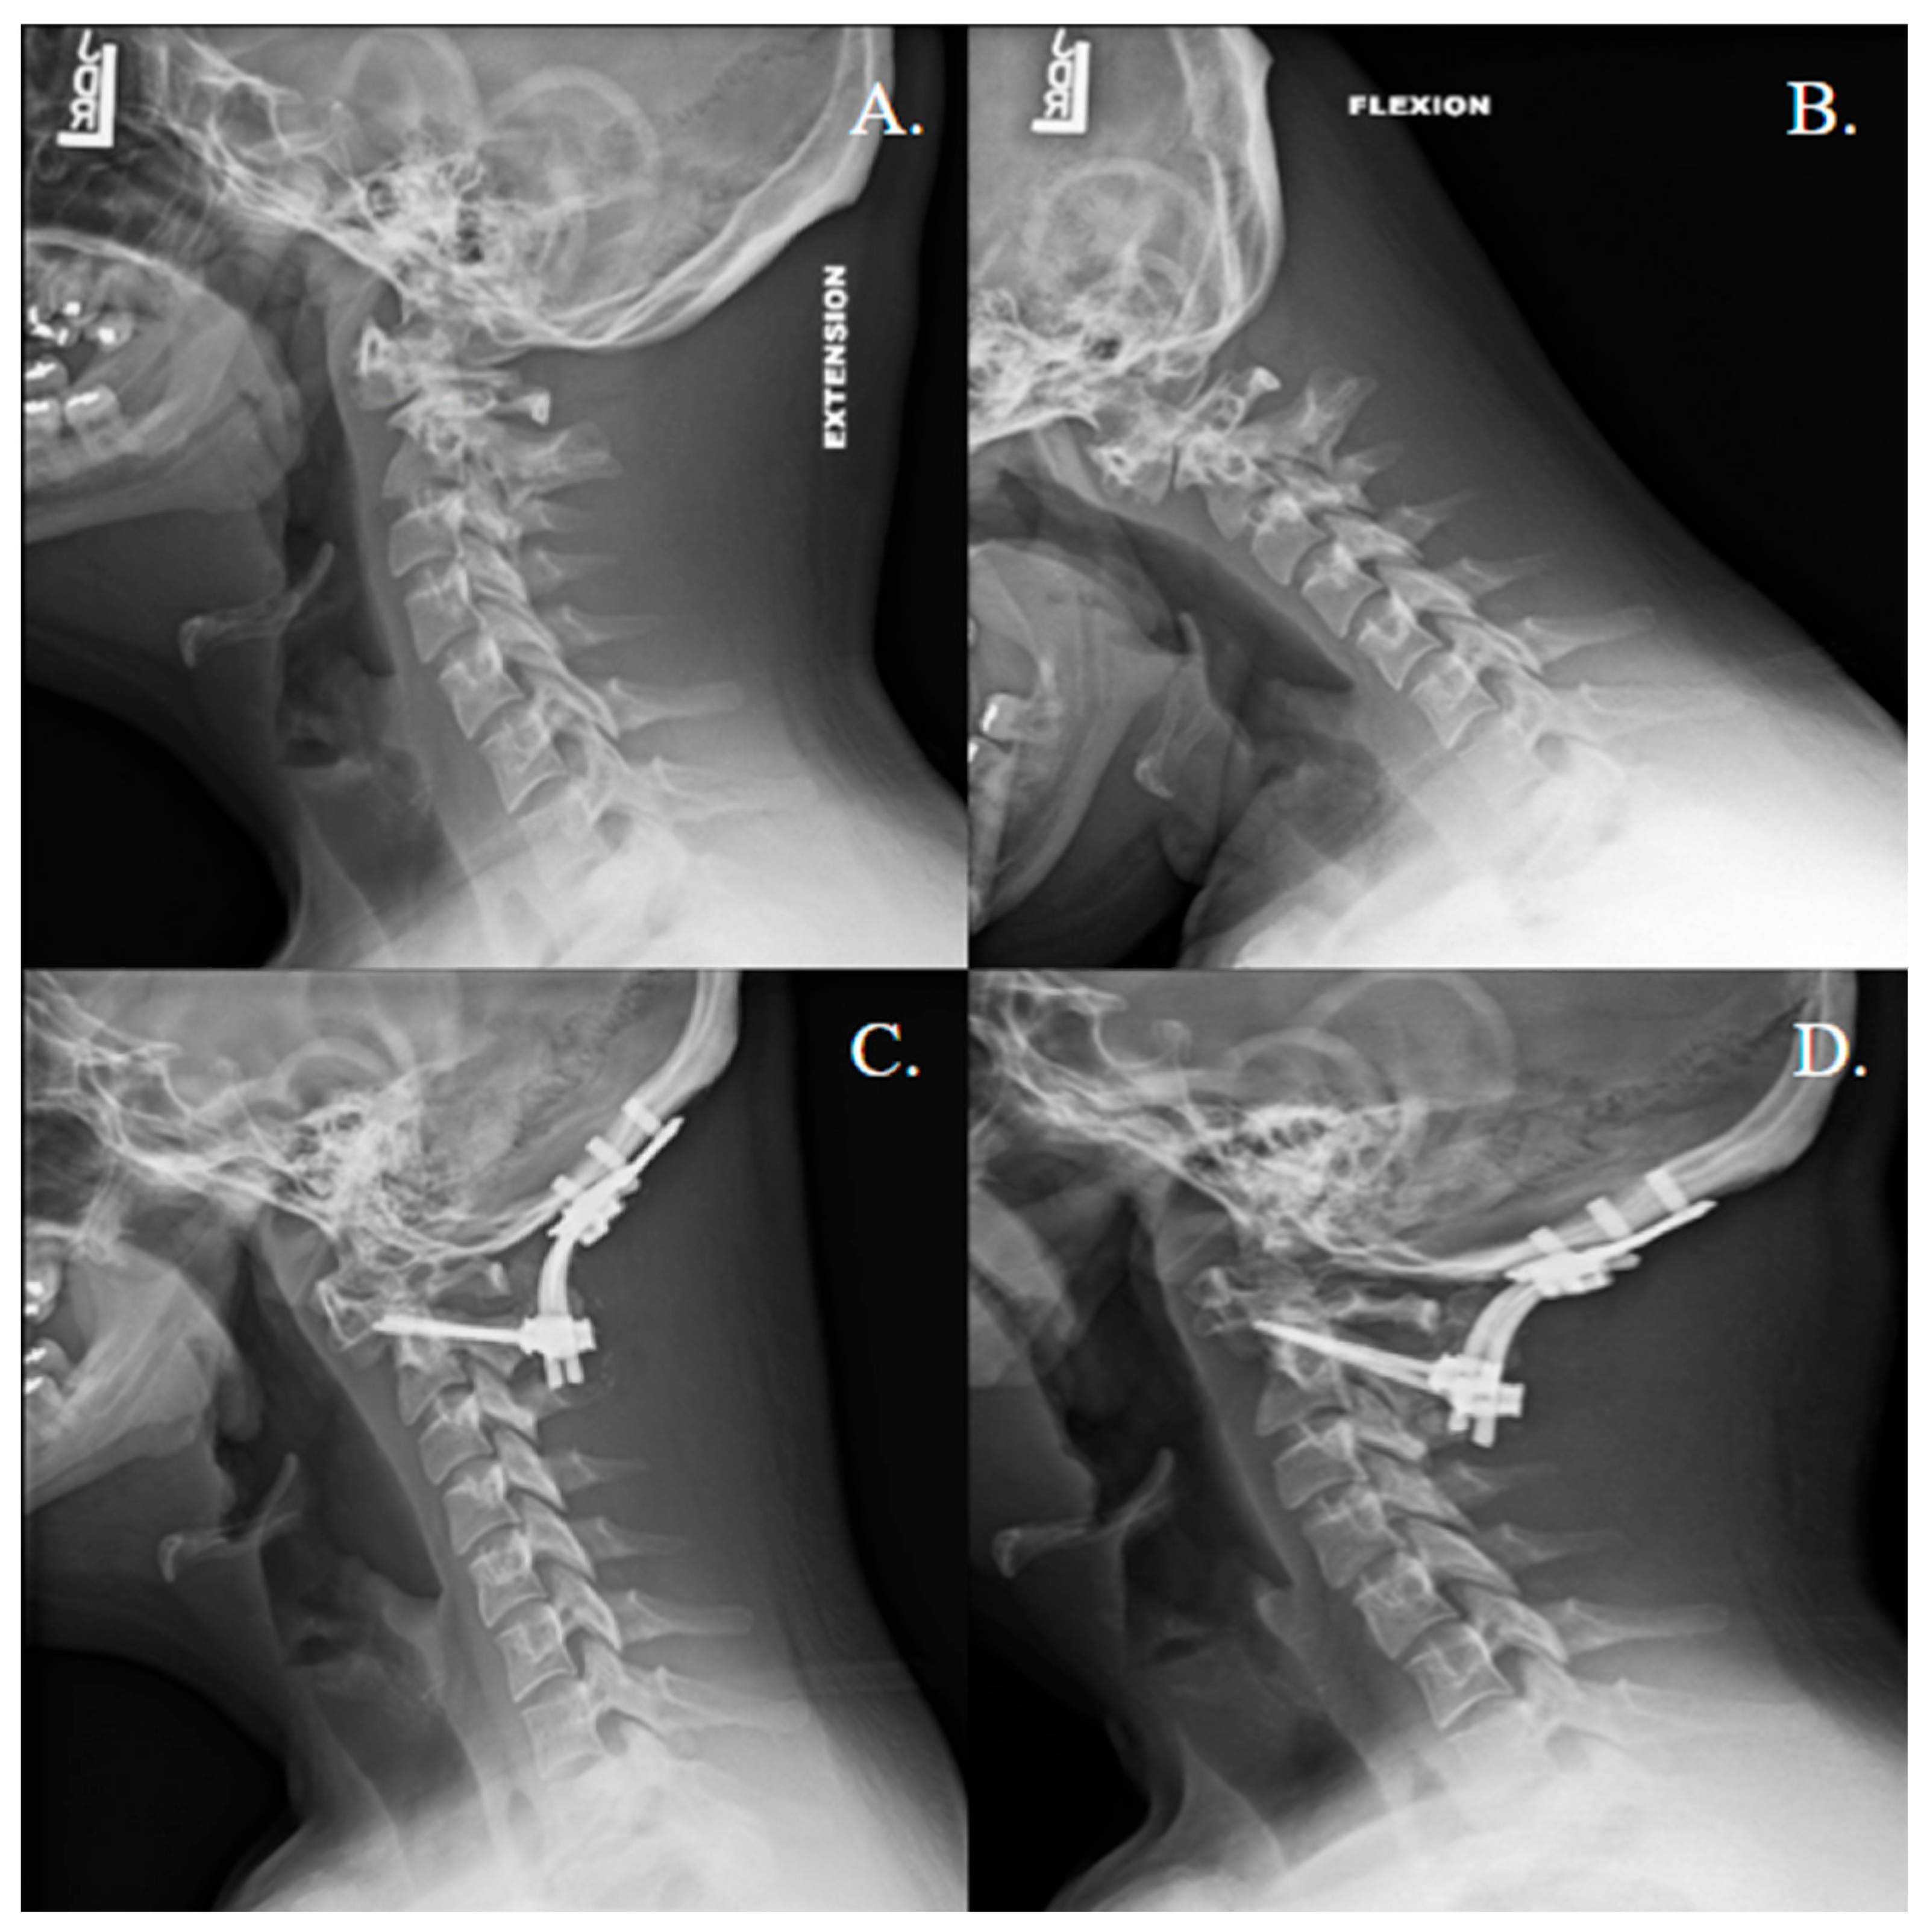

| 1 | 45, M | Degenerative | C1 lateral mass screws bilaterally, C2 translaminar screws bilaterally, titanium rod | N | DBX, rhBMP-2 (XX small kit, 0.82 mg/mL) | 26 |

| 2 | 29, F | Trauma | C1 lateral mass screws bilaterally, C2 translaminar screws bilaterally. Sublaminar Songer cables at C1 and posterior to C2 spinous process, titanium rod | N | DBX, femoral head structural allograft, rhBMP-2 (XX small kit, 0.82 mg/mL) | 25 |

| 3 | 51, M | Trauma | C1 lateral mass screws bilaterally, 1 C2 pars and 1 C2 pedicle screw, titanium rods | N | rhBMP-2 (X small kit, 1.62 mg/mL) | 3 |

| 4 | 28, F | Trauma | C1 lateral mass screws bilaterally, C2 pedicle screws bilaterally, titanium rod | N | DBX, local autograft, rh-BMP-2 (half of a XX small kit, 0.41 mg/mL) | 20 |

| 5 | 80, F | Trauma | C1 lateral mass screws bilaterally, C2 pedicle screws bilaterally, titanium rod, cross connector at C1 | N | DBX, local autograft, rhBMP-2 (X small kit, 1.62 mg/mL) | 4 |

| 6 | 33, F | Trauma | C1 lateral mass screws bilaterally, C2 pedicle screws bilaterally, titanium rod | N | DBX, local autograft, rhBMP-2 (half of a XX small, 0.41 mg/mL) | 69 |

| 7 | 77, M | Trauma | C1 lateral mass screws bilaterally, C2 pedicle screws bilaterally | Y | DBX, local autograft, rh-BMP-2 (XX small kit, 0.82 mg/mL) | 10 |

| 8 | 80, M | Trauma | C1 lateral mass screws bilaterally, C2 pedicle screws bilaterally, titanium rods | Y | DBX, local autograft, rh-BMP-2 (XX small kit, 0.82 mg/mL) | 3 |

| ID | Surgical Complications | Revision (Y/N) | Fusion on Latest Follow-Up Imaging (Y/N) | Atlantoaxial Instability Clinically or in Dynamic Imaging? (Y/N) | Imaging Follow Up (Time, Type) |

|---|---|---|---|---|---|

| 1 | C1 screw breakage | N, avoided re-op due to complete bony fusion | Y | N | 25 months, X-ray |

| 2 | None | N | Y | N | 25 months, X-ray |

| 3 | None | N | Early signs of fusion | N | 3 months, CT |

| 4 | None | N | Y | N | 19 months, CT |

| 5 | None | N | N | N | 4 months, CT |

| 6 | None | N | Y | N | 15 months, X-ray |

| 7 | None | N | Early signs of fusion | N | 3 months, CT |

| 8 | None | N | Early signs of fusion | N | 3 months, X-ray |